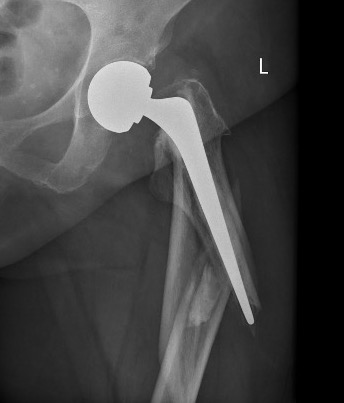

Cemented versus uncemented HA

Cemented unipolar hemiathroplasty Uncemented bipolar hemiarthroplasty

Cement

- minimizes fracture risk in osteoporotic patients

- reduced risk thigh pain

- slightly increased cardiac risk with cement

- RCT of 400 patients

- cemented vs uncemented

- cemented HA had better early mobility

- cemented HA had significantly lower mortality

- no difference in complication or revision rate

- systematic review of 24 RCTs and 3500 patients

- cemented versus uncemented HA

- cemented had less pain and better function

- cemented had fewer fracture / loosening / revision